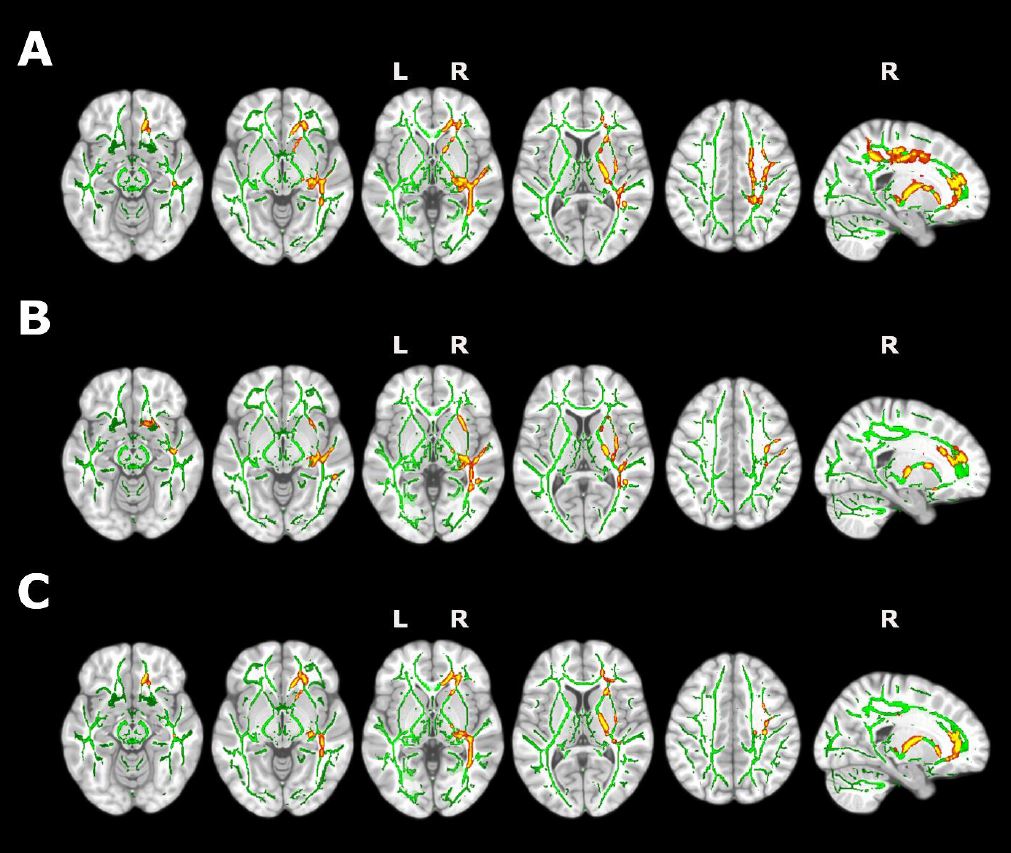

Detectan daño cerebral en pacientes con hernias cervicales mediante técnicas de neuroimagen e inteligencia artificial